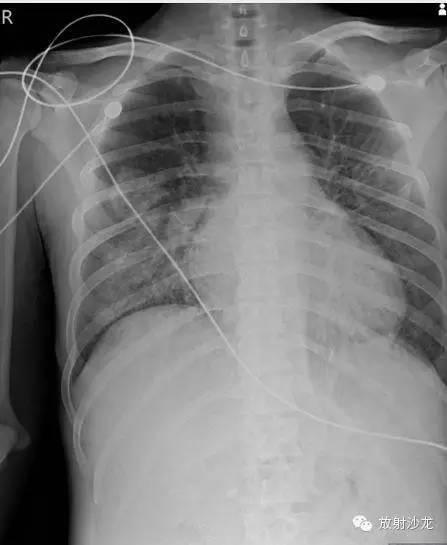

第一次胸片:

(第一次胸片示两肺中野及右肺下野多发斑片状高密度影。胸部CT示多发斑片状磨玻璃样密度增高影以及实变影,同时伴有小叶间隔的增厚。其中有些病灶部分表现为“铺路石征”。两周后CT随访显示这些病灶的密度和范围都增大。电视辅助胸腔镜肺活检下,活检标本病理诊断结果为急性纤维素性机化性肺炎。上述病变经高剂量糖皮质激素治疗三周后明显改善。)